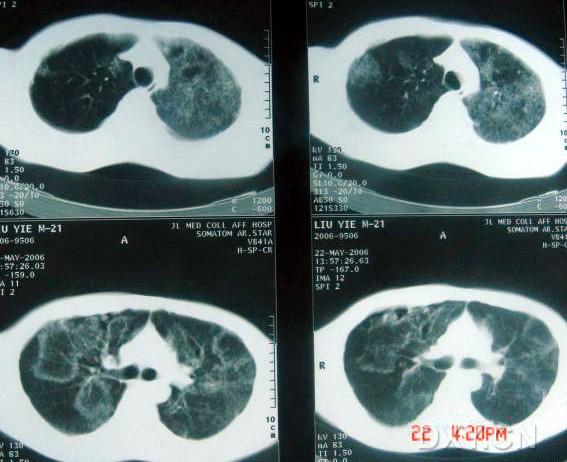

影像表現(xiàn):

兩肺彌漫性顆粒狀陰影,部分陰影融合呈團塊狀,可見支氣管氣相;

呈非對稱,非均勻分布性,部分肺野呈磨玻璃密度;

多處胸膜局限性增厚,胸水征(--)縱隔窗為正常。